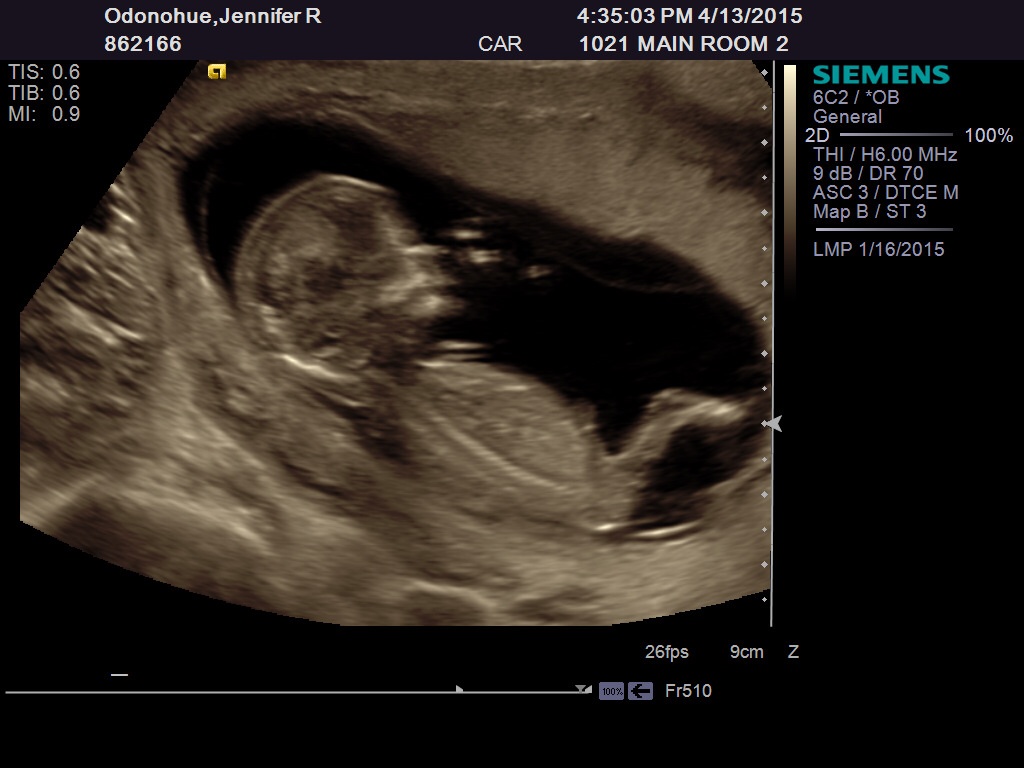

ooh. that is a good one. When I rotate it the nub seems to be high angled but its also looking clean split. Boy looking skull though Good luck!

Maybe boy? Not real confident though. Could be girl looking at the second pic. 50/50 split from me!